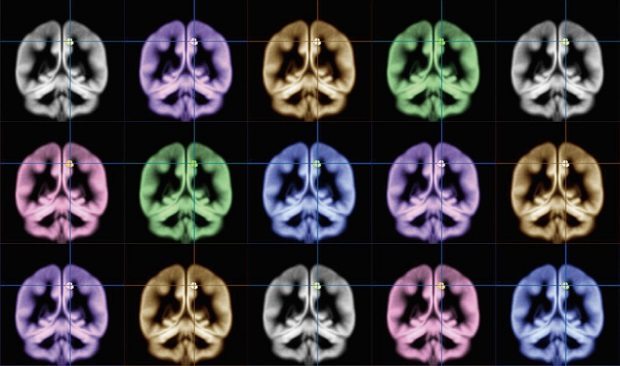

Sato and his team scanned the brains of research participants with MRI. The participants then took a survey that asked how happy they are generally, how intensely they feel emotions, and how satisfied they are with their lives.

Their analysis revealed that those who scored higher on the happiness surveys had more grey matter mass in the precuneus. In other words, people who feel happiness more intensely, feel sadness less intensely, and are more able to find meaning in life have a larger precuneus.

Image: Kyoto University